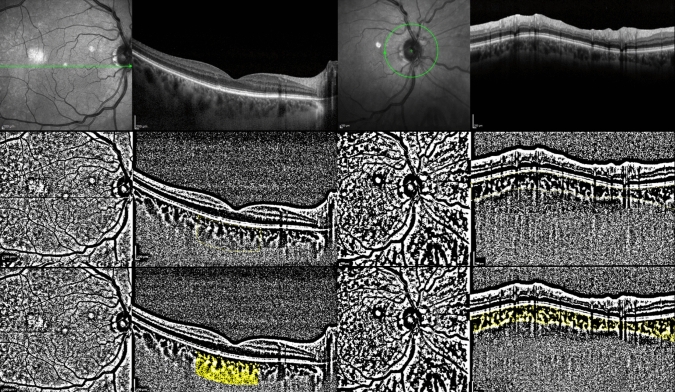

Purpose: To evaluate the relationship between phacoparameters and inflammation parameters (anterior chamber flare (ACF), macular and peripapillary choroidal vascular index (mCVI and pCVI)) changes after cataract surgery.

Study design: Prospective study METHODS: This prospective observational study included patients without systemic and ocular diseases who underwent uncomplicated cataract surgery that may have affected intraocular inflammation. Preoperative, postoperative 1st week, 1st, 3rd and 6th months ACF were measured. At the same visits, mCVI and pCVI were calculated. The relationship between phacoparameters and postoperative ACF, mCVI and pCVI values were evaluated by correlation analysis.

Results: Fifty eyes of 50 patients were included in the study. Postoperative 1st week ACF was significantly higher than preoperative ACF (p<0.001). ACF decreased significantly from postoperative 1st week to 6th months. Postoperative 1st month and 3rd month mCVI were significantly higher than preoperative mCVI (p<0.001, p=0.04, respectively). It was observed that pCVI reached its peak value in the 1st postoperative week and decreased to base value in the postoperative 6th month. A strong positive linear correlation was found between total cumulative dissipated energy (CDE) and the difference between postoperative 1st week and preoperative ACF (p<0.001, r=0.68).

Conclusion: Particularly in the early period after phacoemulsification, ACF, mCVI and pCVI increased. The increase in ACF lost its significance at the third month and the increase in mCVI and pCVI remained significant, which may indicate that the inflammatory effect of cataract surgery lasts longer in the posterior segment. Total CDE can be used to predict postoperative inflammation levels.